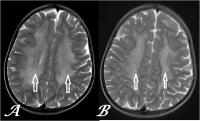

Metachromatic leukodystrophy represents a rare genetic disorder characterized by the accumulation of fatty substances in cells, particularly in the spinal cord, brain, and peripheral nerves. This buildup is due to a deficiency of an enzyme called sulfatides, which aid in breaking down lipids. Based on the age at which symptoms manifest, metachromatic leukodystrophy is of three types: the late infantile form, the juvenile form, and the adult form. Symptoms vary depending on the type but generally include behavioral and personality problems, trouble walking, difficulties in speaking, seizures, etc. The diagnosis of metachromatic leukodystrophy is made through genetic as well as biochemical testing.